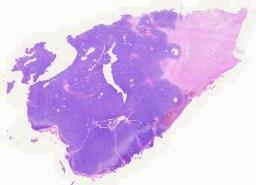

大体所见: 灰黄灰白碎组织一堆,大小3.2 cm×2.5cm×1.5cm,切面灰黄质中,局部见囊壁样物。

临床资料: 女性,37岁,鞍区占位 主诉:停经一年半余 实验室检查: 泌乳素:33.60ng/ml 头颅CT及MRI:脑部核磁共振检查发现鞍区见一不规则肿块,肿块在T1加权图像上呈等密度信号,局部高密度信号(图a);T2加权图像上呈低密度信号(图b);增强后明显强化(图c)。 既往史:患者约1年半前无明显诱因突然停经,余无特殊不适,1年前患者月经仍未来潮,遂至外院就诊,予以雌激素补充对症处理,查泌乳素升高,后患者月经仍未改善,期间出现一过性头痛伴视物模糊,患者再至外院就诊,予以口服溴隐亭治疗。 术中所见:术中鞍底骨质局部隆起变薄,电凝十字切开此处鞍底硬膜,即见肿瘤组织,肿瘤包膜完整,质地不均,肿瘤内有少许豆渣样物,其余组织成分质地韧,与周围结构粘连紧密。